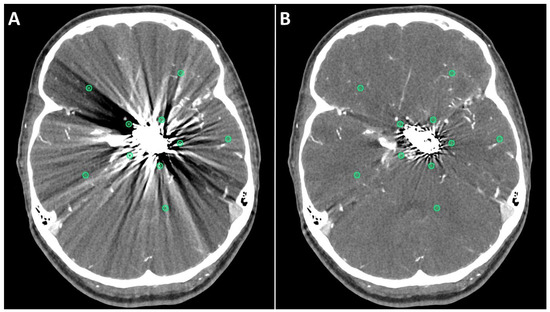

Metal artifact index (MAI) (which was considered to be the mean image noise) was significantly reduced in SEMAR images compared to standard images in close vicinity to (70.9 ± 22.1 vs. 331.8 ± 157.5, respectively) and more distant from the coil package (24.7 ± 6.7 vs. 52.4 ± 20.3, respectively; p < 0.001 each). Figure 2 and Figure 3 demonstrate significantly improved image quality and visualization of arteries after applying the SEMAR algorithm on images with coil-artifacts.

Figure 2.

Exemplary follow up UHR-CT-angiography in axial (A,B) and sagittal (C,D) plane without (A,C) and with SEMAR (B,D) of a 56-year-old female after intracranial coil-embolization of a left sided posterior communicating artery aneurysm. All images were reconstructed as MIP (Maximum Intensity Projection) with 12.5 mm slice thickness. SEMAR significantly improves image quality, even in vessels directly adjacent to the coil package like the anterior communicating artery (white arrow in (B)), the contralateral terminal carotid artery (arrowhead in (B)), the anterior cerebral artery (white arrow in (D)), and the posterior communicating artery (arrowhead in (D)).